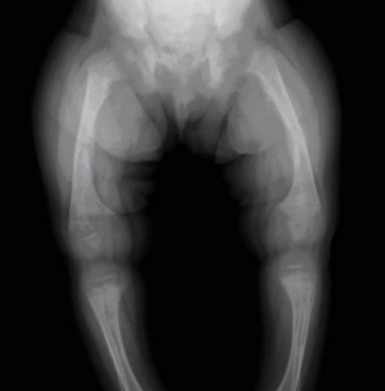

- BBC video on lack of vitamin D- Jan 2012 starts with this following Xray of rickets